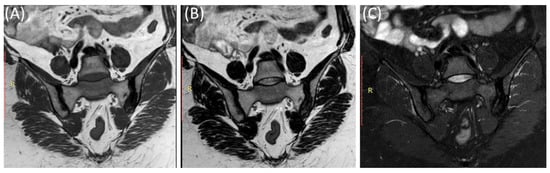

MRI can reveal soft tissue changes, including inflammation of the ligaments and tendons around the SIJ [50]. Enthesitis, which is the inflammation of the insertion points of ligaments and tendons into bone, is a common finding in sacroiliitis and can be visualized [53]. Furthermore, a contrast agent (gadolinium) may be used to enhance areas of active inflammation, making them more visible [54]. In advanced cases, particularly in ankylosing spondylitis (Figure 6), MRI may show evidence of joint ankylosis, where the sacroiliac joint becomes fused [44].

Figure 6.

Coronal T1-WI image (A), coronal T2-WI image (B) and coronal T2-fat suppression image (C) showing sclerosis and mild irregularity in both sacroiliac joints, more on the left side with no evident bone marrow edema in a 52-year-old female with chronic low back and hip pain suggestive of bilateral chronic sacroiliitis.

As shown in Figure 7, fat suppression techniques or fat saturation sequences are often used in MRI to suppress the signal from fat tissue, making it easier to identify areas of inflammation and edema [55,56].

Figure 7.

Coronal T1WI image (A) and STIR image (B) showing edema and irregularity in the left sacroiliac joint in a 47-year-old female with lower back pain and left sciatica with acute (active) sacroiliitis.